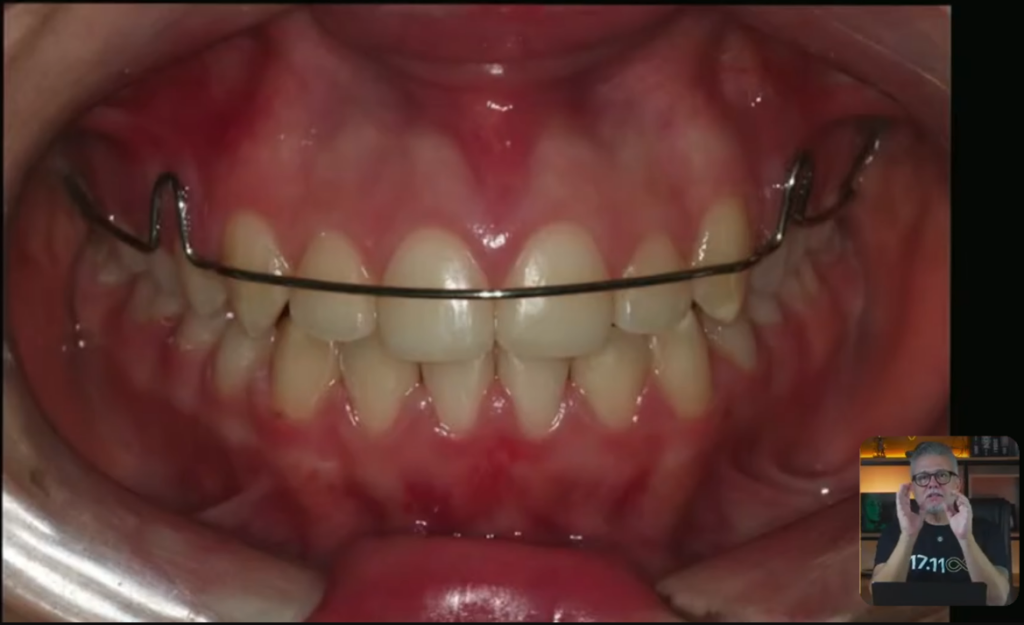

E aí, quando você termina um tratamento como esse aqui, você vai lá e coloca uma contenção.

Esses dentes que vocês estão vendo aqui, super alinhados, então eu coloco essa contenção fixa superior em todos os meus pacientes:

Vocês estão percebendo que é uma contenção higiênica colocada nos dentes superiores, que não vai causar esse problema. Engraçado, né?

Porque colocam tanta culpa na contenção higiênica, que ela causa retração de gengival.

Mas eu nunca vi uma contenção higiênica causar esse problema nos dentes superiores.